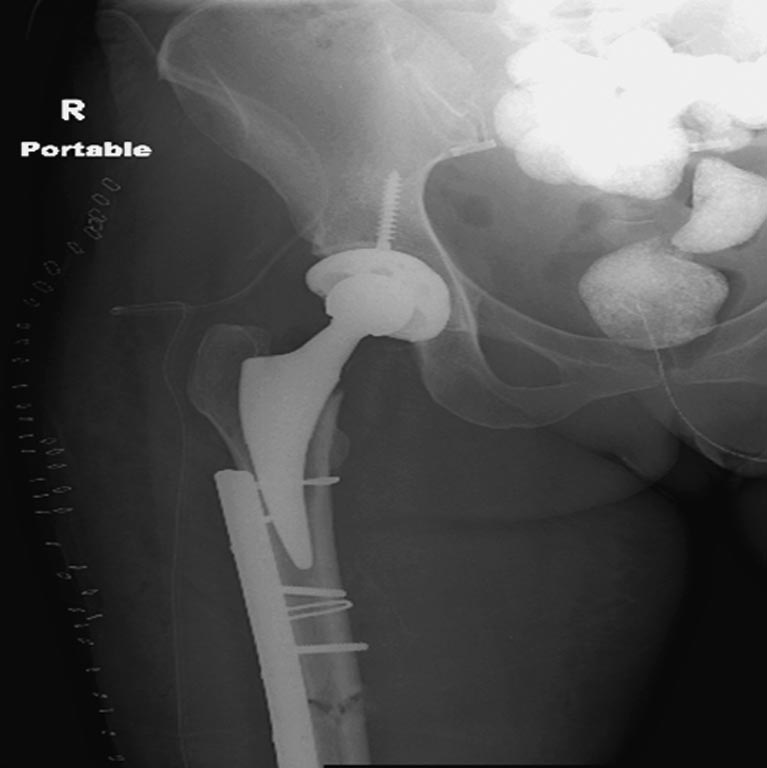

На 25 день с момента травмы операция на Jackson table с боковым обширным

доступом. Удаление стержней с местной обработкой. В тазобедренном

суставе удаление головки, на дне вертлужной впадины полная отслойка

хряща. Вертлужный компонент с одним винтом и короткая ножка -  Fitmore

press fit stem. На второй день однократно доза радиации для профилактики

Выписана. Нагрузку разрешили на левой стороне, а полная в 3 мес.  Здесь

снимки при амбулаторном наблюдении​: послеоперационно, 2 мес, 3 мес и 6

мес. Нагрузка полная, отсутствует хромота, и нет жалоб.